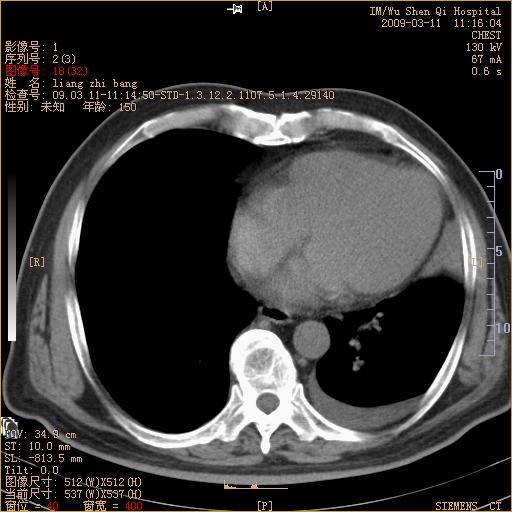

标题: CT18604:男,60岁,咳嗽一月余 [打印本页]

标题: CT18604:男,60岁,咳嗽一月余

1)考虑左肺上叶中央型肺癌并左肺上叶肺不张;建议必要时行纤支镜检查进一步明确诊断。2)左侧胸腔积液。

肺门肿块、支气管开口闭塞伴肺不张及胸水!典型的中心型肺癌变现!

1、左肺上叶中央型肺癌并上叶阻塞性肺不张。

2、左侧胸腔少量积液,右侧胸膜轻度增厚。

左肺们肿块并左肺上叶不张。考虑左肺中心性肺癌并左肺上叶不张及左侧胸腔积液